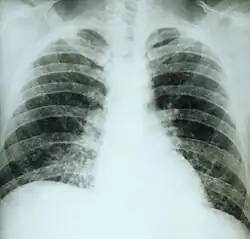

Чаще всего встречается острый гистоплазмоз лёгких, вызываемый аэрогенным инфицированием. Острые формы лёгочного гистоплазмоза могут протекать бессимптомно и обнаруживаться лишь по результатам кожного теста с гистоплазмином, по положительным результатам серологических реакций, иногда по петрификатам в лёгких и прикорневых лимфатических узлах. При лёгких формах, которые преобладают, самочувствие больных остаётся хорошим, нередко они продолжают работать, лихорадка отсутствует или бывает кратковременной (3-4 дня), а общая длительность лечения 2-3 недели. При рентгенологическом исследовании выявляют усиление рисунка и увеличение тени корней лёгких, лишь у отдельных больных наблюдаются мелкоочаговые тени, преимущественно в нижних отделах лёгких.

Тяжелые формы острого гистоплазмоза лёгких характеризуются внезапным началом, быстрым повышением температуры тела до 40-41 °С. Температурная кривая неправильного типа с большим суточным размахом. Потрясающие ознобы сменяются диффузным потоотделением. Больные жалуются на сильную головную боль, слабость, боли в мышцах и костях, кашель, боли в груди. У некоторых больных отмечаются тошнота, рвота, понос, боли в животе. Длительность лихорадки 2-6 недели. В периоде реконвалесценции длительно наблюдается субфебрилитет, астенизация, резкое снижение трудоспособности, потливость. Эти явления сохраняются до 1 года. При перкуссии лёгких можно отметить некоторое укорочение звука, при аускультации — мелкопузырчатые влажные хрипы, преимущественно в нижних отделах лёгких. Рентгенологически выявляют крупно- и среднеочаговые тени в виде «ватных хлопьев», которые могут сливаться. В дальнейшем инфильтраты полностью исчезают или на их месте образуются очаги фиброза и кальцинации.

Хронический гистоплазмоз лёгких протекает в виде длительной прогрессирующей болезни, периодически дающей обострения. Наблюдают умеренную лихорадку, кашель с мокротой, при рентгенологическом исследовании выявляются каверны, фиброз и множественные кальцинированные очаги.